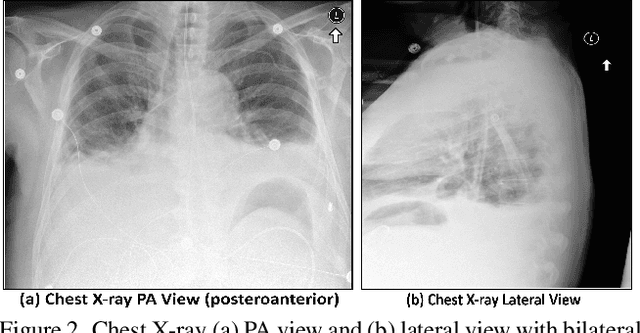

Abstract:Large Language Models (LLMs) are increasingly applied to medical imaging tasks, including image interpretation and synthetic image generation. However, these models often produce hallucinations, which are confident but incorrect outputs that can mislead clinical decisions. This study examines hallucinations in two directions: image to text, where LLMs generate reports from X-ray, CT, or MRI scans, and text to image, where models create medical images from clinical prompts. We analyze errors such as factual inconsistencies and anatomical inaccuracies, evaluating outputs using expert informed criteria across imaging modalities. Our findings reveal common patterns of hallucination in both interpretive and generative tasks, with implications for clinical reliability. We also discuss factors contributing to these failures, including model architecture and training data. By systematically studying both image understanding and generation, this work provides insights into improving the safety and trustworthiness of LLM driven medical imaging systems.